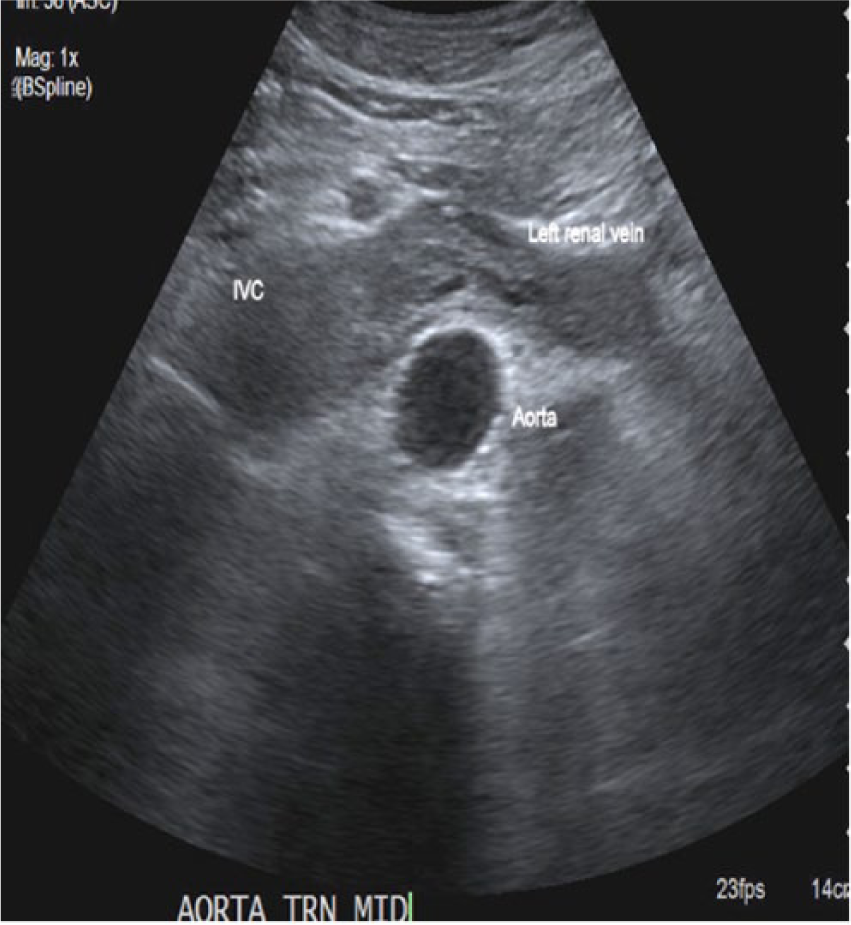

An elderly man in his early seventies was referred to the hospital as an outpatient to undergo an abdominal aortic aneurysm (AAA) screening. The patient had a history of smoking for 20 years. The sonographic examination was performed on an Acuson 2000 ultrasound system (Siemens, Washington, DC), with a curved array C5-2 probe (2-5 MHZ bandwidth). Sonographic findings showed no evidence of an AAA. Velocities and Doppler waveforms throughout the abdominal aorta were normal and showed no significant stenosis. During the examination, the sonographer observed echogenic material in the area of the inferior vena cava (IVC). Upon further examination, the IVC appeared to be thrombosed (Figures 1 and 2). Color Doppler imaging was used to confirm that the IVC was partially obstructed (Figure 3). A transverse view of the IVC and aorta also showed a thrombus in the left renal vein (Figure 4). This prompted the sonographer to extend the examination to the left kidney where a partially exophytic mass located on the anterior/superior portion of the left kidney was seen (Figures 5 and 6). The mass measured 5.43 cm long, 5.31 cm wide, and 4.30 cm anterior-posterior (AP) dimension. Color Doppler imaging showed significant vascularity within the mass (Figure 6). The findings were suspicious for renal cell carcinoma, and the patient shortly thereafter had additional testing with a computed tomography (CT) scan of the abdomen and pelvis with contrast. The CT scan confirmed a mass in the left kidney with direct tumor extension into the left renal vein. A thrombus was seen in the IVC both above and below the level of the renal veins. However, it could not be determined by imaging if the thrombus was related to bland thrombus rather than tumor thrombus. Also noted in the CT findings were prominent venous collaterals in the retroperitoneal region centrally and on the left. The patient had a complete left nephrectomy, and the placement of an IVC filter was also performed. The pathology report confirmed a 6.0 cm multifocal renal cell carcinoma with a large tumor extension into the left renal vein. The tissue histology using a hematoxylin and eosin stain showed a Fuhrman Grade 3 tumor, and the cancer was noted to be of a conventional clear cell type, which is the most common.

Transverse view of the abdominal aorta showing thrombus in left renal vein extending into the inferior vena cava.